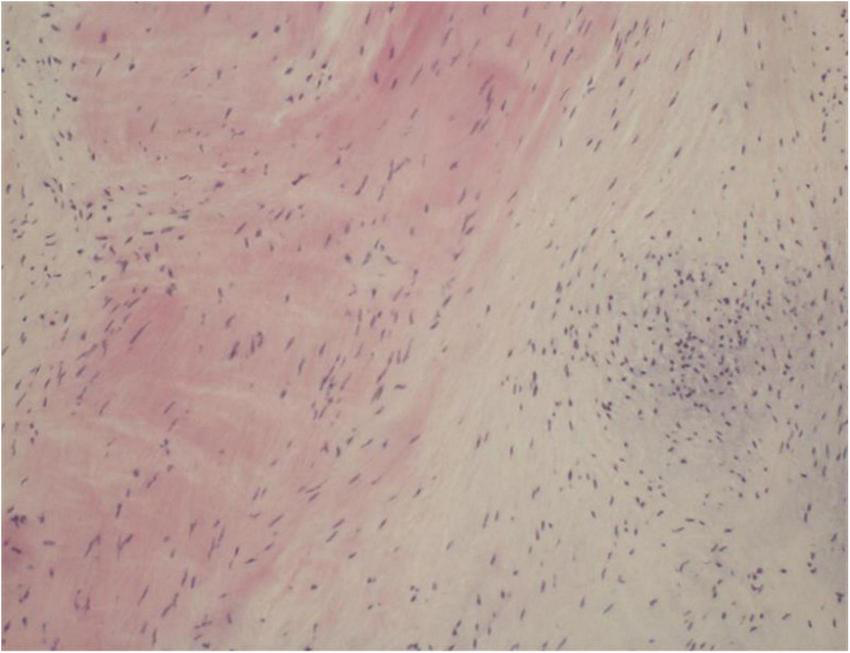

One year later, the patient again sought medical care due to chest tightness and shortness of breath for 2 months. Chest X-ray and chest CT were normal. Additionally, cardiac auscultation revealed a grade 3/6 apical systolic murmur. Follow-up TTE showed thickening and fibrosis of the anterior and posterior mitral valve cusps, mild stenosis (transmitral mean gradient of 3 mmHg and mitral valve area of 2.6 cm2) and moderate to severe regurgitation of the mitral valve (Figure 3) with EROA of 0.40 cm2 and the regurgitant volume of 58 mL. The other valves were normal. The left ventricular function was normal, with a left ventricular ejection fraction (LVEF) of 64%. Repeated blood cultures were again negative. Mitral valve mechanical valve replacement was then performed, which intraoperatively revealed thickening and multiple small nodular vegetations on the mitral valve. No perforation or destruction of the mitral valve was identified. Histopathology demonstrated fibrous tissue hyperplasia with hyaline degeneration and no inflammatory cell infiltration (Figure 4). Postoperatively, oral prednisolone acetate and warfarin were administered with an international normalized ratio (INR) target of 3.0–4.0. During her 17-month follow-up, the patient was clinically stable, the symptoms of cerebral infarction were relieved, and no new infarct was found on the follow-up brain CT. TTE revealed no mitral regurgitation with normal ventricular function.

FIGURE 4

Histopathology of excised valve demonstrating fibrous tissue hyperplasia with hyaline degeneration and no inflammatory cell infiltration.